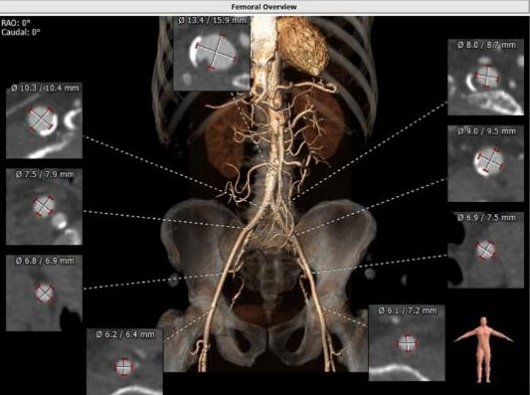

主动脉CTA:三叶瓣,瓣环面积为518 mm²,严重钙化;法式窦结构可,主动脉瓣瓣环周径82.3 mm,平均直径26.2mm,左室流出道周径28.0mm,主动脉窦管交界处(STJ)高28.9 mm;左冠高度14.8mm,右冠高度17.2mm,升主动脉未见明显增宽,主动脉根部角度44°,左室大(66.9mm),心尖部局部心肌薄弱,推荐右侧股动脉做为主入路。推荐使用26号瓣膜。

周玉杰教授、王志坚教授与多学科团队会诊讨论后,考虑患者冠脉钙化较重,术中可能会应用旋磨、激光技术,一站式手术风险较大,遂决定先行PCI术,择期选用爱德华SAPIEN 3 球扩式瓣膜行TAVR术。因患者为多瓣膜疾病,心脏扩大,血压极低,心功能较差,术中、术后极有可能出现循环崩溃,因此决定由心外科、体外循环ECMO团队全程为TAVR手术保驾护航。